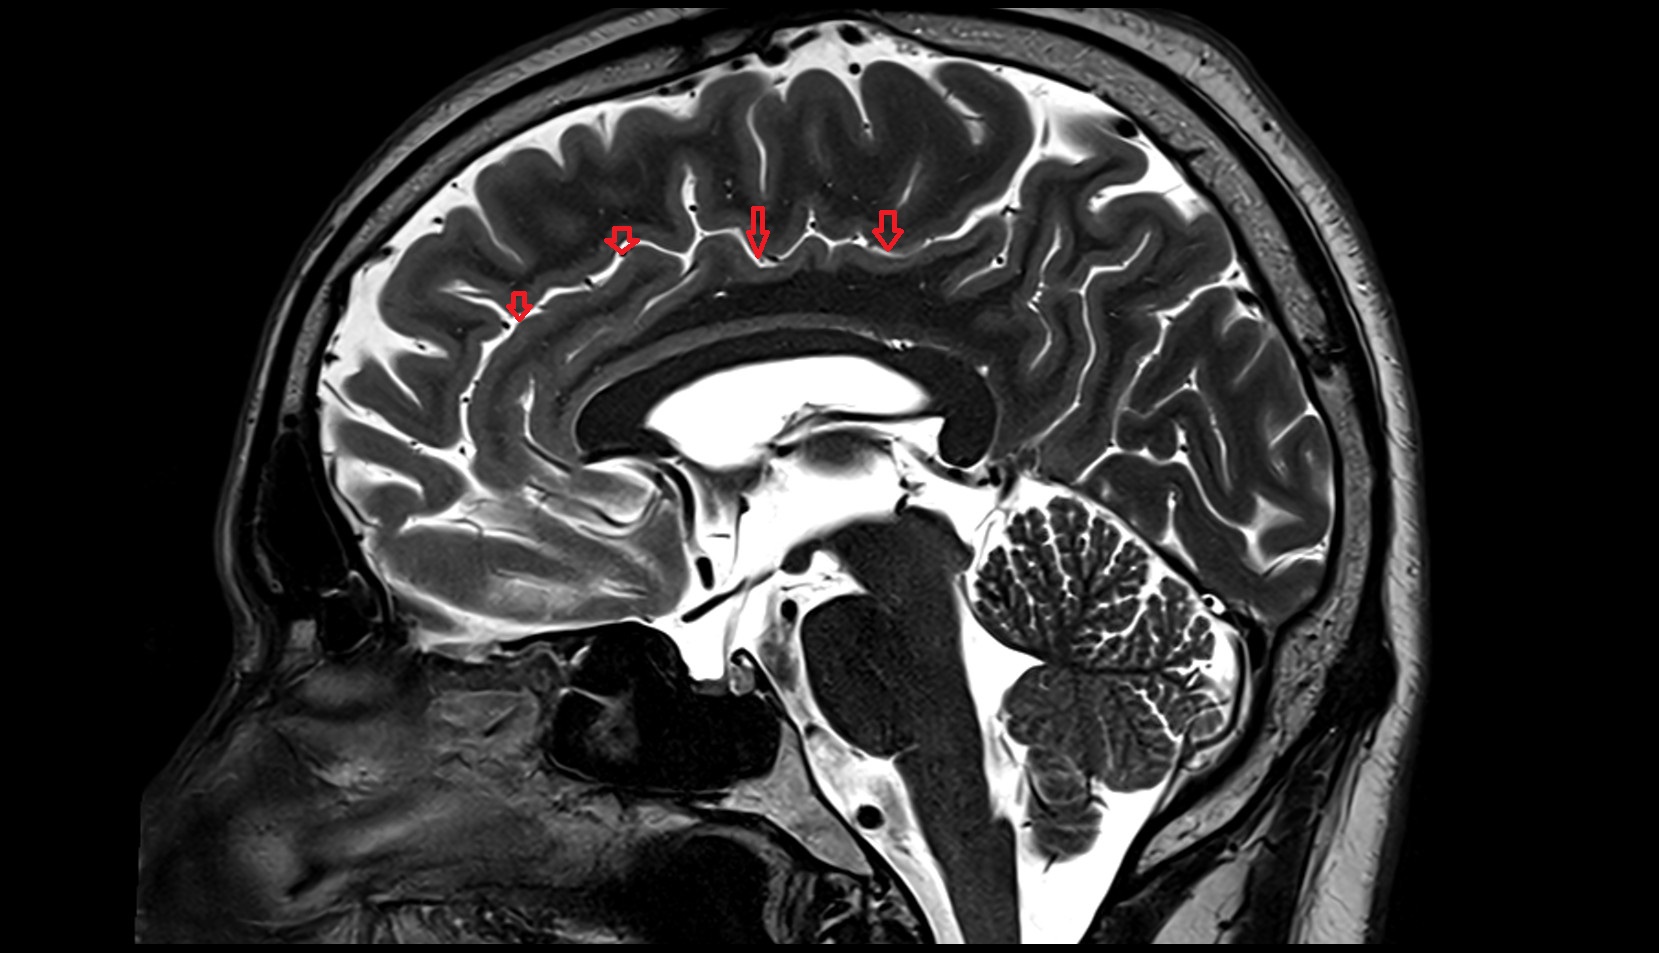

- Central sulcus

- Cingulate sulcus